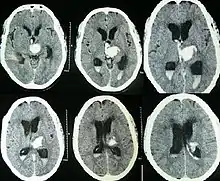

Hemorragia intracerebral espontânea com hidrocefalia na tomografia computadorizada[6]

Tanto a angiografia por tomografia computadorizada (ATC) como a angiografia por ressonância magnética (ARM) demonstraram ser efetivas no diagnóstico de malformações vasculares intracranianas após a hemorragia intracerebral.[13] Com tanta frequência, um angiograma de tomografia computadorizada será realizado para excluir uma causa secundária de hemorragia[14] ou para detectar um "sinal local".

A hemorragia intraparenquimatosa pode ser reconhecida na tomografia computadorizada porque o sangue aparece mais brilhante do que outro tecido e é separado da mesa interna do crânio por tecido cerebral. O tecido que envolve um sangramento é muitas vezes menos denso do que o resto do cérebro por causa do edema e, portanto, aparece mais escuro na tomografia computadorizada.[14]

Para hemorragia intracerebral espontânea vista na tomografia computadorizada, a taxa de mortalidade é de 34-50% em 30 dias após o dano,[6] e metade das mortes ocorrem nos primeiros 2 dias.[26] Embora a maioria das mortes ocorra nos primeiros dias após a doença, os sobreviventes têm um excesso de mortalidade em longo prazo de 27% em comparação com a população em geral.[27]